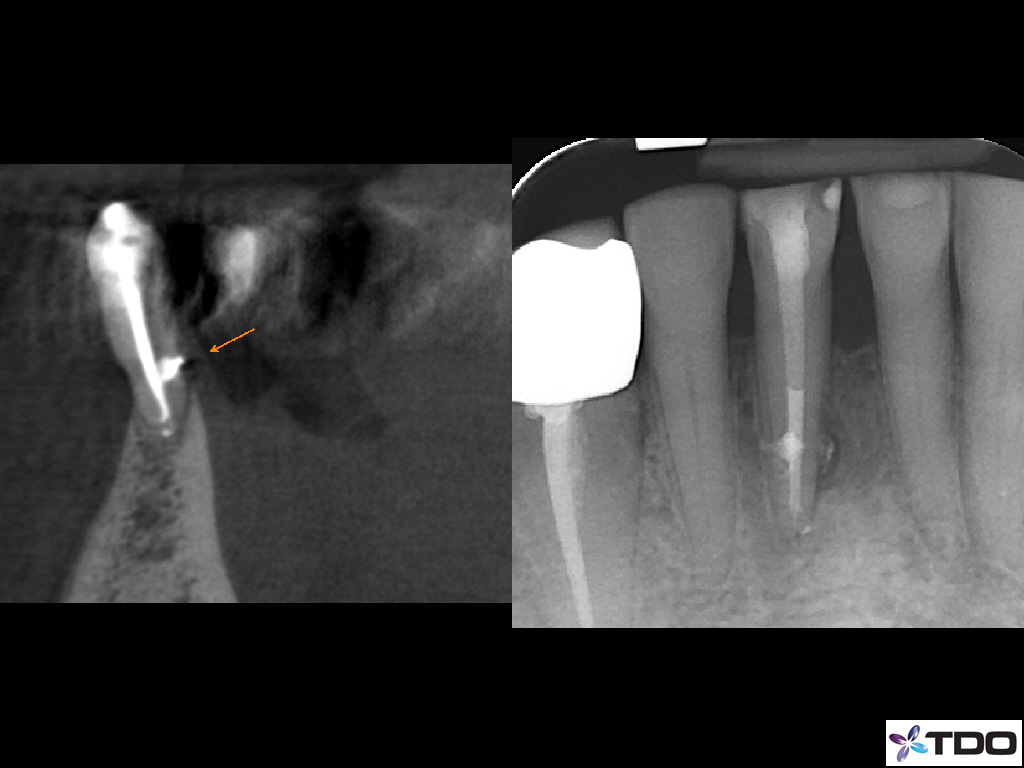

Blog Image